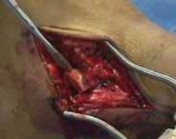

After completing the lateral approach, the surgeon carefully evaluates the lateral process fracture ( TECH FIG 5A,B).

1.

I gently displace the fracture and assess the condition of the subtalar joint.

2.

Small fragments are commonly devoid of soft tissue attachments. Only very small fragments should be removed.

3.

Larger fragments, even those without soft tissue attachments, are needed to restore the structure of the lateral process in any closed fracture of the lateral process of the talus.

40.

Any anterior or posterior osteochondral fragments are reduced and provisionally fixed with small, smooth Kirschner wires.

A Freer elevator is helpful to determine the anatomic subtalar joint line.

Final reduction of the direct lateral fragments of the lateral process is provisionally fixed by Kirschner wires.

41.

Isolated lateral process fractures are best fixed by interfragmentary mini-screw fixation.

42.

Comminuted fractures should be buttressed by mini-screw and plate fixation to resist displacement against axial loads to the process ( TECH FIG 5C,D).